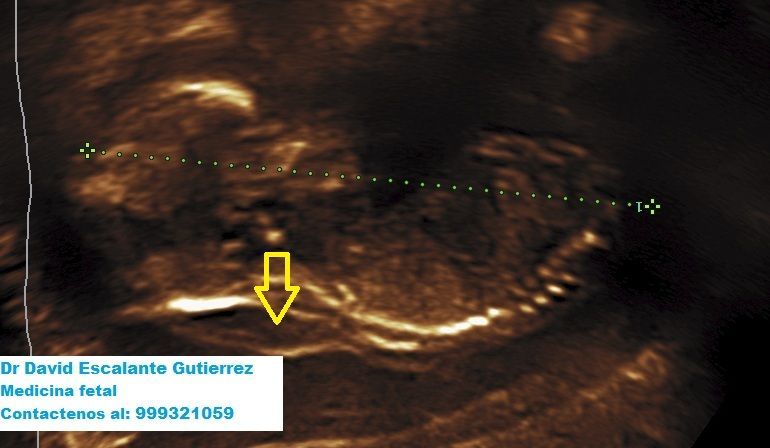

Realizamos las ecografías de viabilidad del embarazo, genética, morfológica, de bienestar fetal, ecocardiografías fetales, así como procedimientos invasivos como biopsia de vellosidades coriales y amniocentesis.